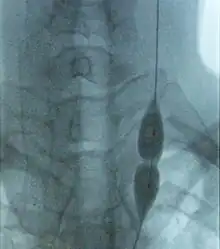

Balloon angioplasty and stenting have been proposed as treatment options for CCSVI in MS. The proposed treatment has been termed "liberation therapy" though the name has been criticized for suggesting unrealistic results.[14]

Balloon angioplasty in a preliminary, uncontrolled, unblinded study by Zamboni improved symptoms in MS in a minority of treated people.[44] Although the procedure pushes the vein open temporarily, the effect does not persist,[22] supporters advise against using stents.[45]

Venous percutaneous transluminal angioplasty (PTA) has proven to be safe but due to its ineffectiveness is not recommended.[15]